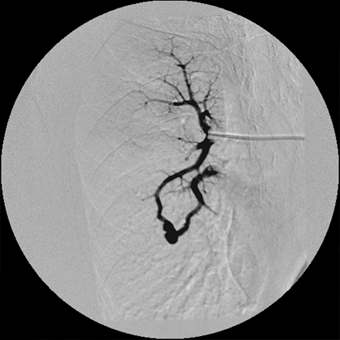

血管撮影にて

異常血管を確認

金属コイルにて

異常血管を塞栓し消失